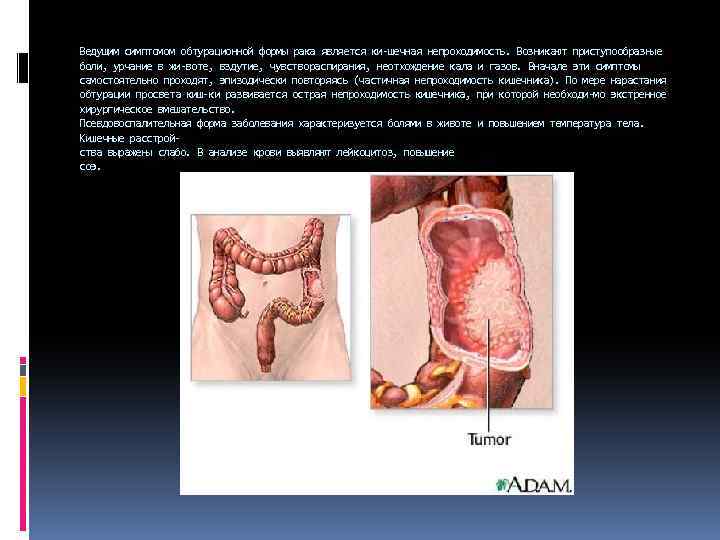

Ведущим симптомом обтурационной формы рака является ки шечная непроходимость. Возникают приступообразные боли, урчание в жи воте, вздутие, чувствораспирания, неотхождение кала и газов. Вначале эти симптомы самостоятельно проходят, эпизодически повторяясь (частичная непроходимость кишечника). По мере нарастания обтурации просвета киш ки развивается острая непроходимость кишечника, при которой необходи мо экстренное хирургическое вмешательство. Псевдовоспалительная форма заболевания характеризуется болями в животе и повышением температура тела. Кишечные расстрой ства выражены слабо. В анализе крови выявляют лейкоцитоз, повышение соэ.